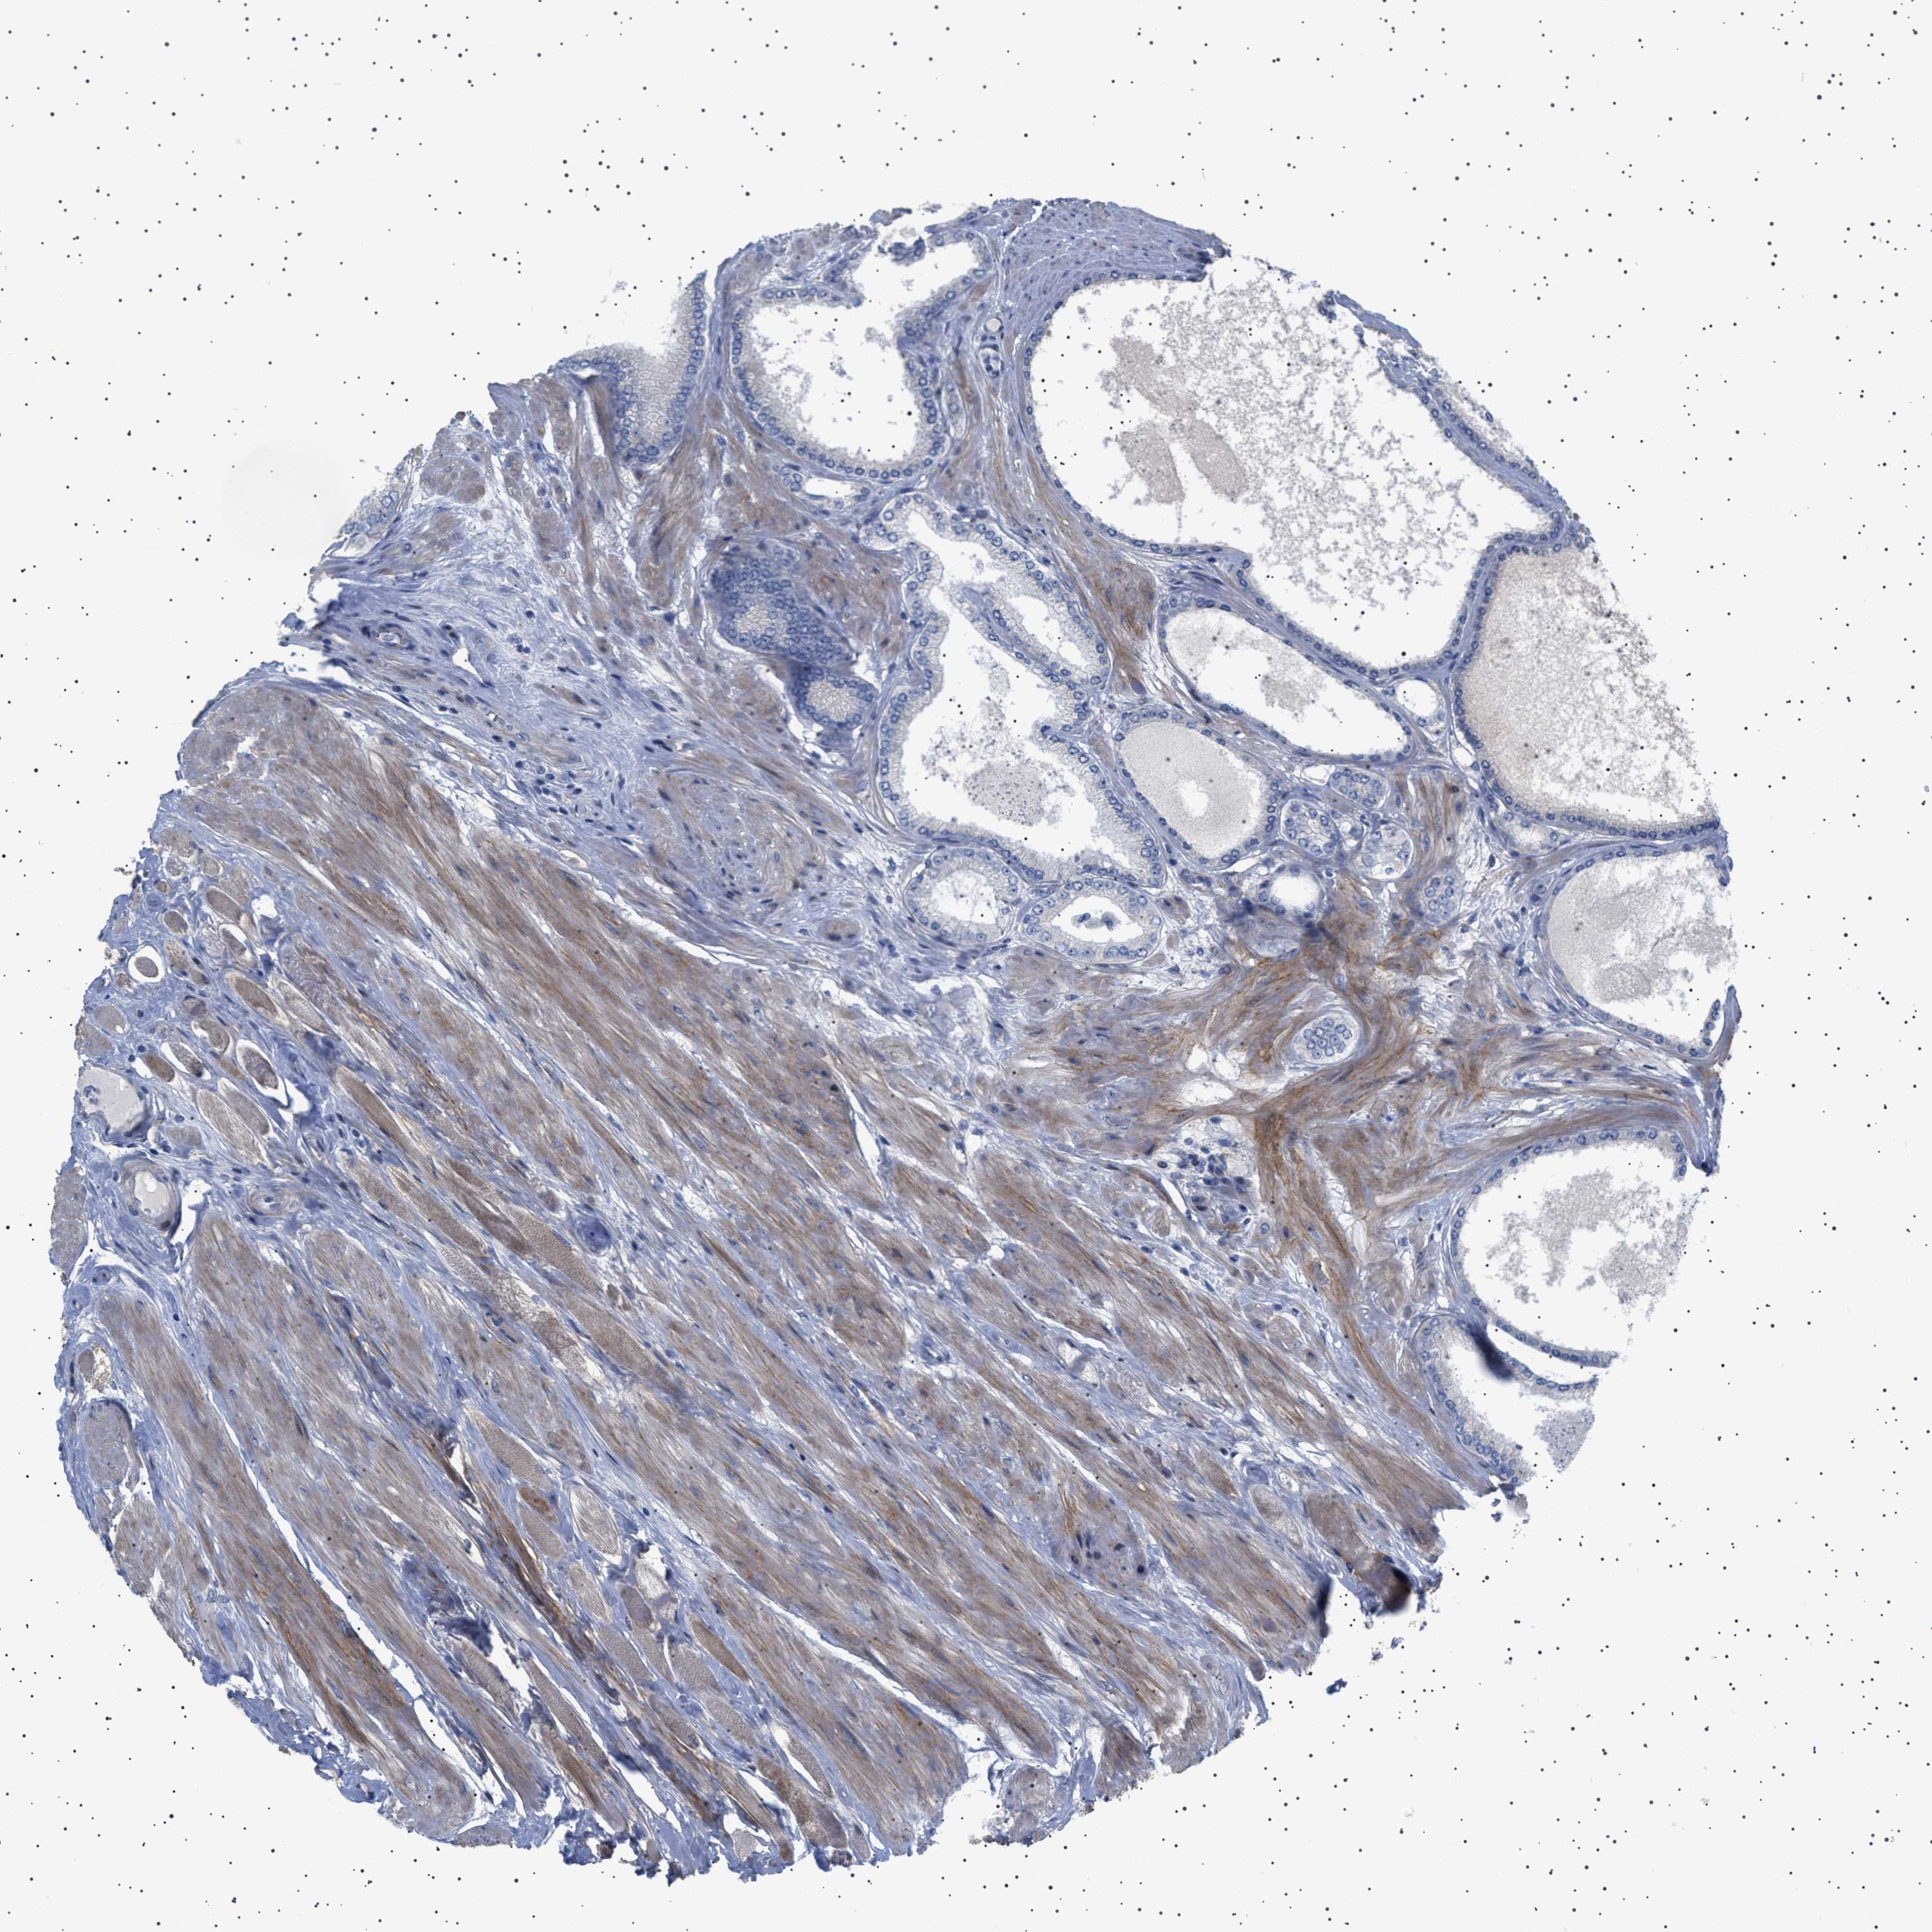

PROSTATE CANCER - Protein expressioni

A mouse-over function shows sample information and annotation data. Click on an image to view it in a full screen mode. Samples can be filtered based on level of antibody staining by selecting one or several of the following categories: high, medium, low and not detected. The assay and annotation is described here.

Note that samples used for immunohistochemistry by the Human Protein Atlas do not correspond to samples in the TCGA dataset.

Antibody stainingi

Antibody staining in the annotated cell types in the current human tissue is reported as not detected, low, medium, or high, based on conventional immunohistochemistry profiling in selected tissues. This score is based on the combination of the staining intensity and fraction of stained cells.

Each image is clickable and will lead to virtual microscopy that enables deeper exploration of all samples and also displays staining intensity scores, fraction scores and subcellular localization as well as patient and tissue information for each sample.

Antibody HPA018073

Staining

High

Medium

Low

Not detected

Intensity

Strong

Moderate

Weak

Negative

Quantity

>75%

75%-25%

<25%

None

Location

Nuclear

Cytoplasmic/membranous

Cytoplasmic/membranous,nuclear

Adenocarcinoma, High grade

Adenocarcinoma, Low grade